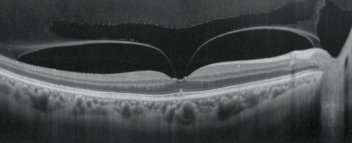

Retinal Mode

Choroidal Mode

Selectable OCT sensitivity

Selection of the appropriate OCT sensitivity allows acquisition of B-scan images through media opacities.